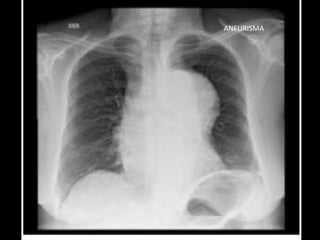

ANEURISMA

RADIOGRAFIA • Radiografía normal •Radiografía patológica – Ensanchamiento mediastinal • Técnica radiográfica • Estructuras normales de tamaño o distribución atípica • Estructuras vasculares • Tumores